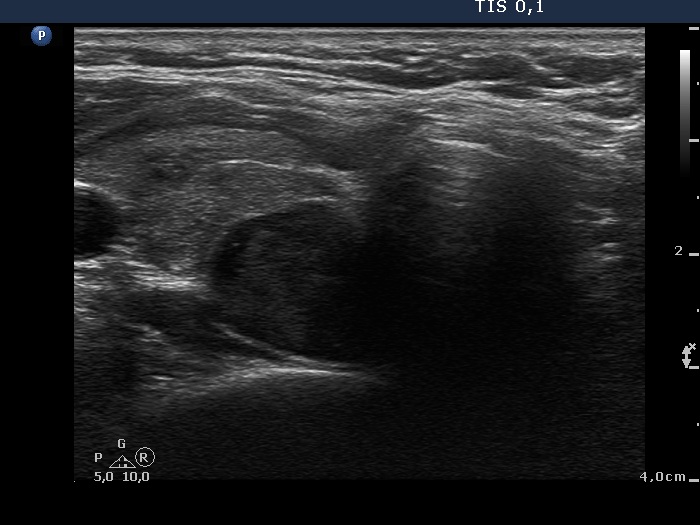

Ultrasonography: The thyroid was echonormal and contained multiple inhomogeneous, hyperechogenic nodules. There was a hypoechogenic lesion in the dorsal part or dorsal to the lower pole of the right lobe.

Aspiration cytology resulted in benign lesion which might correspond to parathyroid adenoma.